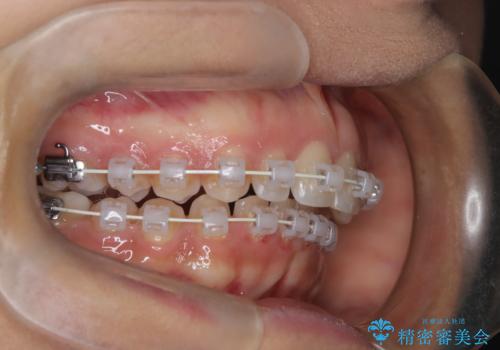

本症例では、非抜歯での治療を選択したため、スペースを確保するためにIPR(歯間削合)を行い、歯列を整えました。オーバージェット(上の前歯と下の前歯の水平的なズレ)は残る結果となりましたが、見た目や機能の改善を重視し、患者様と治療計画を共有しながら進めました。治療中は、歯列全体のバランスと噛み合わせを考慮しつつ、矯正装置の適切な使用を徹底しました。当初の計画通りに治療を完了し、患者様にも満足していただけました。